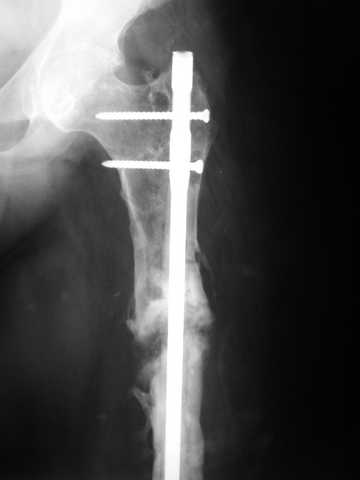

Мы демонтировали спице-стержневой аппарат, рассверлили костно-мозговой канал (до 14 мм), установили в канал спейсер с антибиотиком и произвели его блокирование четырьмя винтами ( рис. 1, 2, 3, 4).

В качестве армирующего элемента для спейсера мы использовали титановый неканюлированный штифт типа UFN (диаметр 9 мм, длина 400 мм). Проксимальную широкую часть штифта костным цементом не покрывали (рис. 5).

Дистальные блокирующие отверстия в цементе рассверлили после его застывания под ЭОП'ом. В проксимальном отломке использовали винт-полер (так как штифт проходил очень близко к переднему кортикальному слою).

В остальном, операция прошла без технических трудностей. Александр Николаевич, спасибо за ваши прекрасные развертки. Так не хочется отдавать их Вам обратно! Завтра пациент выписывается. Температура тела и анализы у него нормальные. Бедро мягкое, отечность тканей значительно уменьшилась. Послеоперационные раны зажили первичным натяжением. Укорочение конечности составляет 1,5 см (по ощущениям больного, это оптимальная длина ноги для него, так как у него анкилоз коленного сустава и голеностопного сустава в положении подошвенного сгибания). Пациент ходит с дозированной нагрузкой на конечность (10% от веса тела). Свищ на передне-наружной поверхности средней трети бедра, который открылся за неделю до последней операции рядом со стержнем аппарата, закрылся 5 дней назад (рис. 6,7, 8).